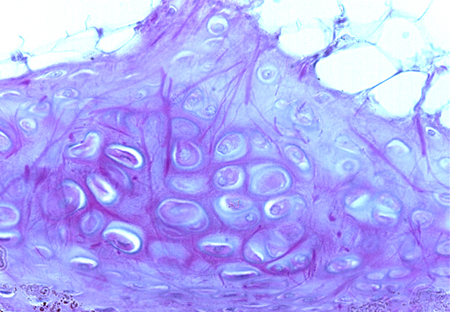

In both images, observe a elastic fibers in the cartilage extracellular matrix, as well as chondrocytes (several are highlighted in the upper image when you move the cursor over it).

External ear. Staining: Weigert. Magnification: medium.